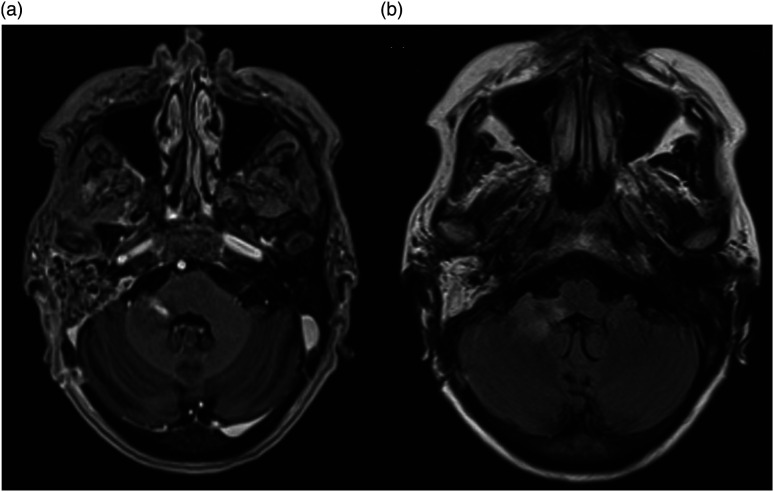

据报道,小脑脓肿是慢性化脓性中耳炎(CSOM)的一种并发症,有时会危及生命。小脑脓肿通常是由慢性化脓性中耳炎通过盆骨的骨质侵蚀或乙状窦的血栓性静脉炎直接传播引起的。然而,通过颅神经的解剖桥将感染从隐骨传播到小脑的另一种途径以前可能从未被描述过。一名患有 CSOM 和胆脂瘤的 63 岁女性患者出现共济失调和右侧面瘫。计算机断层扫描(CT)显示右侧耻骨骨质侵蚀,提示中耳感染。对比后磁共振成像显示,肿胀的第 7/8 神经复合物增强,提示神经炎,右侧岩骨有胆脂瘤。磁共振成像还显示同侧小脑脚有环形强化病变,提示脑脓肿。紧急进行了手术治疗,并抽出了脓液。随后,耳鼻喉科团队还为她进行了乳突切除术和胆脂瘤切除术,最终她的病情有所好转。本病例说明,CSOM 可通过颅神经的解剖桥传播感染而导致小脑脓肿,而不会直接从颞骨或鼻窦血栓性静脉炎侵入。

Cerebellar abscess is a reported complication of chronic suppurative otitis media (CSOM) and is life threatening at times. It usually develops by direct spread of CSOM through the bony erosion in the petrous bone or by thrombophlebitis of the sigmoid sinus. However, an alternative pathway of infection transmission from the petrous bone to the cerebellum through the anatomical bridge of the cranial nerves has possibly not been described before. A 63-year-old female patient with CSOM and cholesteatoma developed ataxia and right facial palsy. Computed tomography (CT) showed bone erosion of the right petrous bone suggesting middle ear infection. Post-contrast MRI revealed an enhancement of swollen 7th/8th nerve complex, suggesting neuritis, and cholesteatoma in the right petrous bone. It also showed ring enhancing lesion in the cerebellar peduncle of the same side suggesting brain abscess. Surgical intervention was performed emergently and pus aspirated. She also underwent mastoidectomy and removal of cholesteatoma later by the otolaryngology team and finally got better. This case illustrates that CSOM can cause cerebellar abscess by spreading infection via anatomical bridge of the cranial nerves without direct invasion from the temporal bone or thrombophlebitis of sinus.